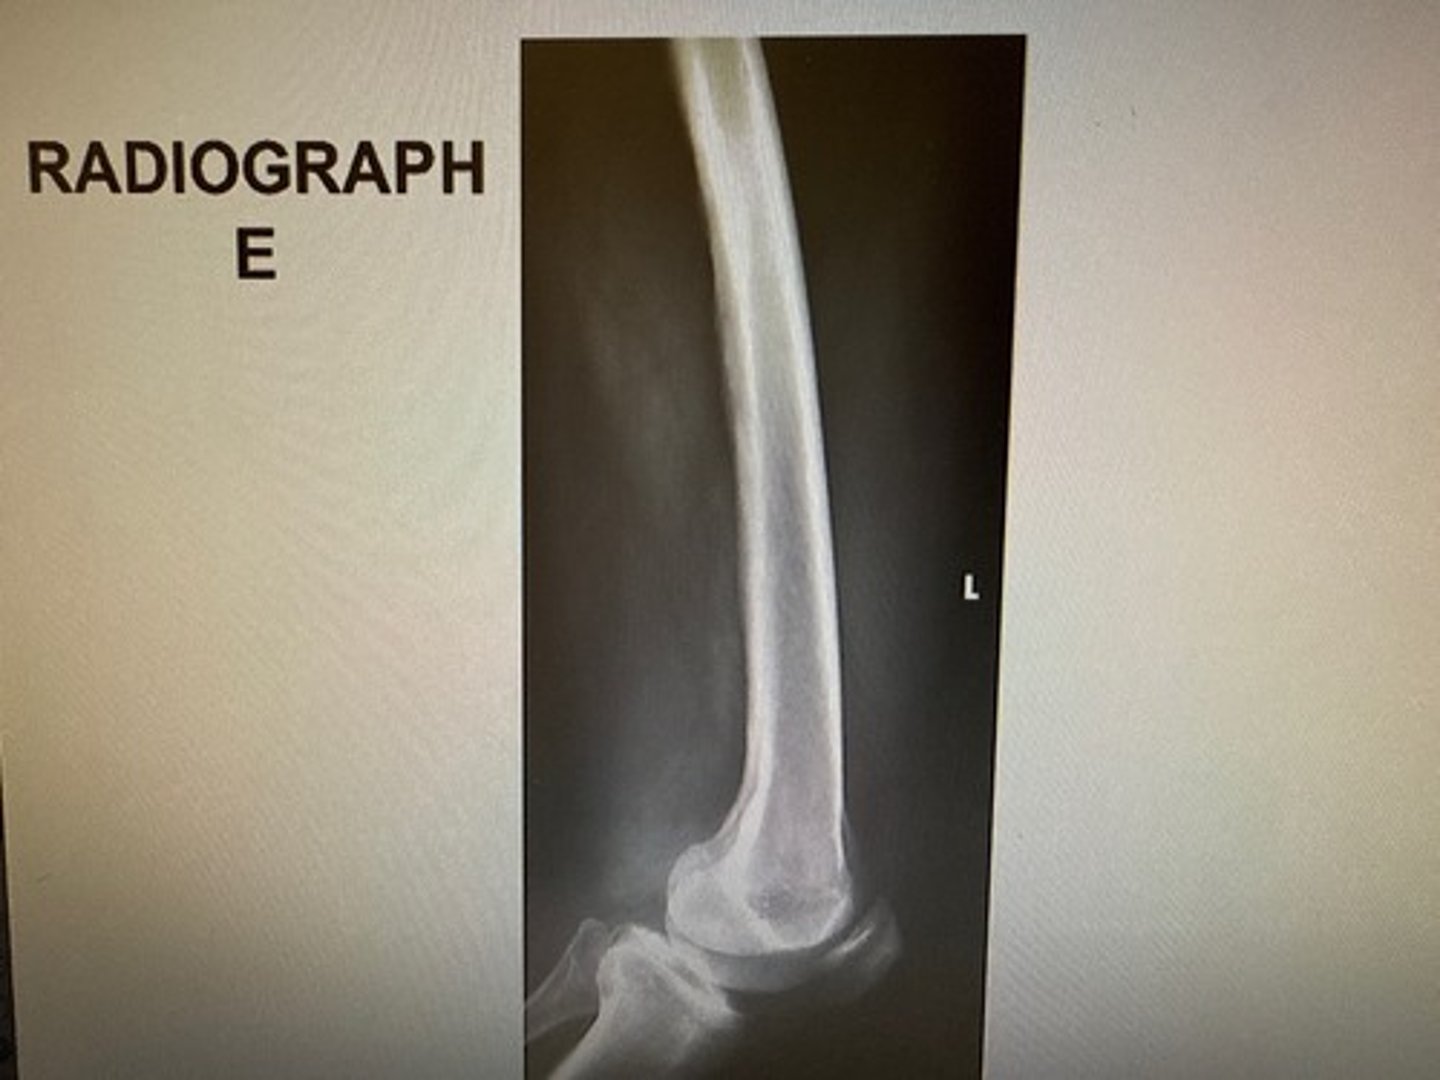

Identify this projection:

AP femur

AP pelvis

AP hip

Modified Cleaves

Choose three reasons why the inferior condyles are not SI on this image:

The med condyle is inferior to the lat condyle

Poor positioning

No angle on the CR

Poor centering

The divergence of the beam